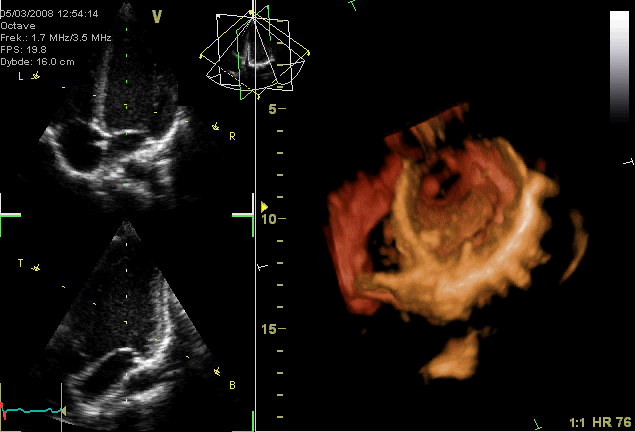

Abnormal heart sounds may indicate problems with the health of the valves. Heart murmurs sound like a "whoosh" or "slosh" and indicate regurgitation or backflow of blood through the valves because they cannot close properly. Heart murmurs are common and generally not serious, but some may be more severe and/or caused by severe underlying problems within the heart. Murmurs may also be caused by valve stenosis (improper opening) and cardiac shunts, a severe condition in which a defect in the septum allows blood to flow between both sides of the heart.